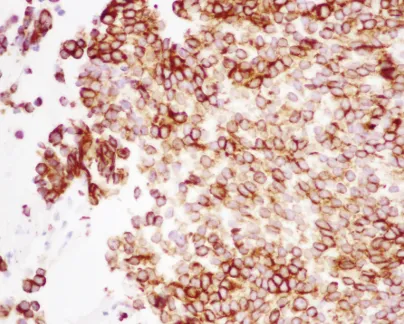

还可见明显的凋亡和坏死区域,以及带有纤维黏液样变区域的血管化肿瘤间质。免疫组织化学显示波形蛋白和广谱细胞角蛋白染色阳性(图6)。

图6:显微照片(40倍放大),显示广谱细胞角蛋白弥漫阳性免疫组织化学染色。